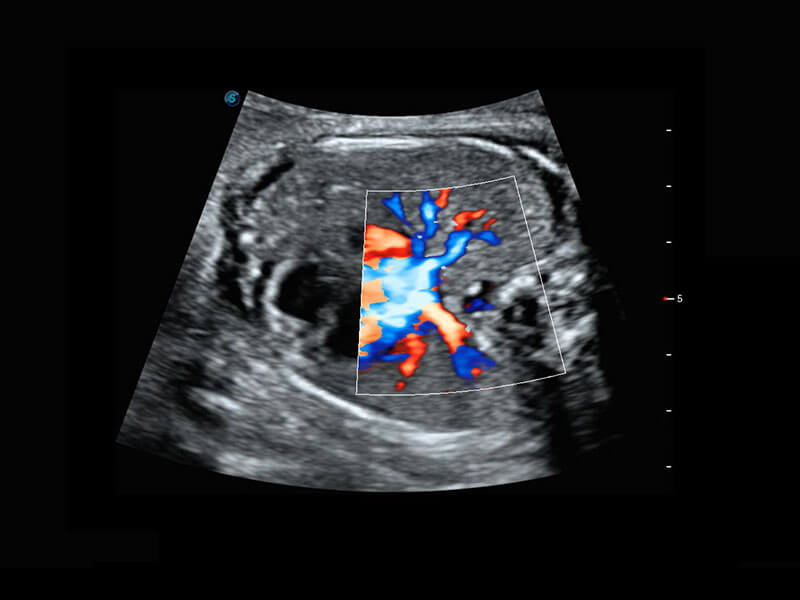

P60搭载宽频带线阵探头、宽景成像、弹性成像技术,为您提供乳腺应用方案。P60支持高频相控阵探头、线阵探头、腹部高频探头、腹部微凸探头等,丰富的探头群搭载敏感的彩色血流成像,适用于新生儿多种脏器检测要求,满足新生儿筛查需求。

新生儿肝血管癌

新生儿脊髓圆锥

新生儿心脏